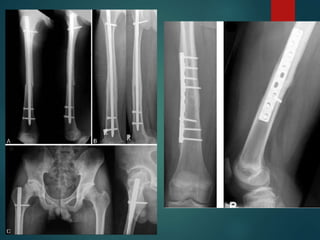

Femoral Shaft Fx

 Treatment Options

 IM Nail with locking screws

 ORIF with plate/screw construct

 External fixation

 Consider traction pin if prolonged delay to surgery

Distal Femur Fractures

 Distal Metaphyseal Fractures

 Look for intra-articular involvement

 Plain films

 CT

 Treatment:

 Retrograde IM Nail

 ORIF open vs. MIPO

 Above depends on fracture type,

bone quality, and fracture

location